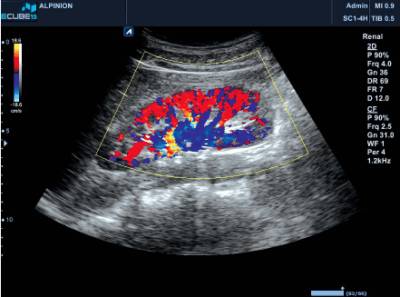

МРТ (магнитно-резонансная томография) будет наиболее информативным исследованием, поскольку дает возможность увидеть опухоль в трех измерениях.

Ангиография, исследование с помощью введения вещества, реагирующего на рентгеновские лучи, позволит выяснить особенности кровоснабжения опухоли, порядок, количество ответвлений сосудов.

Иногда вместо ангиографии применяют особый вид обследования МР-ангиографию, при которой не нужно вводить в сосудистое русло контрастных веществ.